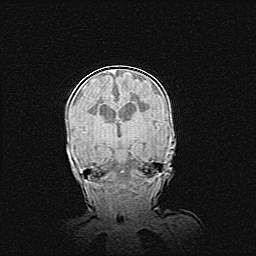

Наружная гидроцефалия с возможной атрофией височных областей.

Возраст: 28 дней

Вес: 3670 г

Пол: мужской

Окружность головы: 38 см

Срок гестации: 40 недель

Гидроцефалия головного мозга у новорожденных – это заболевание, которое характеризуется скоплением избыточного количества спинномозговой жидкости в желудочковой системе головного мозга в результате затруднения её перемещения от места выработки к месту поглощения в кровеносную систему или вследствие нарушения абсорбции. При открытой наружной форме гидроцефалии у новорожденных расширяются и переполняются субарахноидные пространства.

При нормотензивных  формах,  которые,  как  правило,  являются  следствием  перенесенных ишемических  повреждений  паренхимы  мозга,  возможно  сочетание микроцефалии  с нормотензивной гидроцефалией. В основе данных изменений лежит атрофия больших полушарий с преимущественной  локализацией  в  лобно-височных  областях.